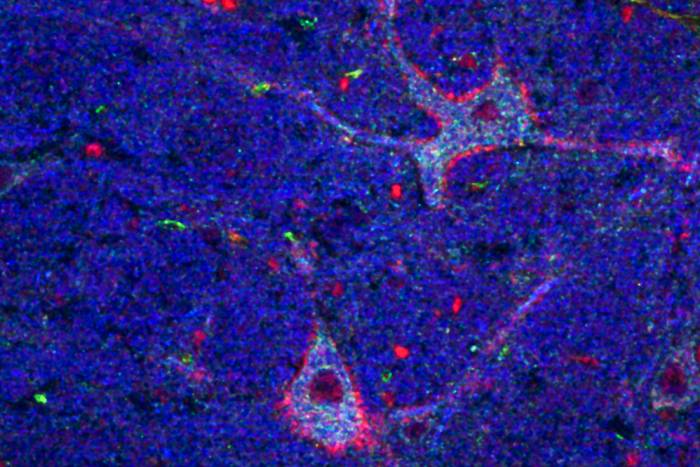

By analyzing gene expression patterns, researchers have identified previously unknown distinctions between mouse and human neurons. They have also developed a new way to track cellular changes associated with brain disorders.